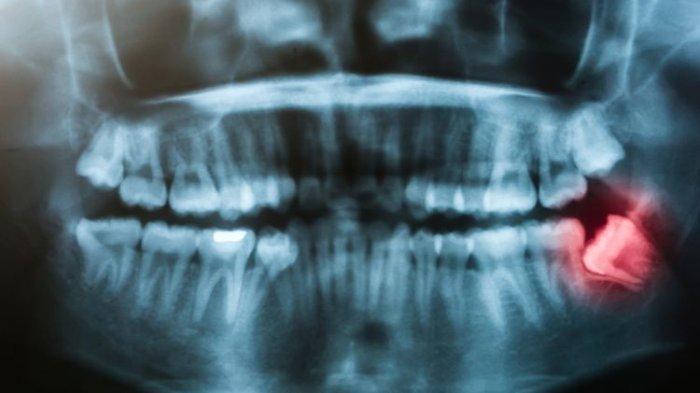

Impaksi tersebut juga bisa dalam keadaan miring secara vertikal maupun horizontal.

Keadaan intinya gigi impaksi yaitu kondisi gigi yang tidak erupsi secara normal.

Sedangkan pada pemeriksaan klinis atau objektifnya, nampak pada daerah gigi tersebut tidak mengalami erupsi sempurna mungkin hanya terlihat sebagian atau sama sekali tidak terlihat.

Posisi gigi yang mengalami impaksi juga tidak seperti gigi dengan erupsi normal lainnya.

Dr. drg. Munawir menyampaikan, untuk lebih jelasnya bisa dilakukan pemeriksaan penunjang lainnya seperti pemeriksaan radiograph foto rontgent sehingga dapat terlihat jelas posisi dari gigi tersebut.